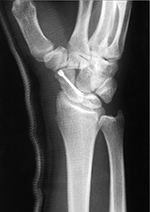

| Herbert screw |

Herbert screws |

Herbert screw |

| Note the different screw pitch on each end. From Benjamin, 1994

|

Also know as headless (recessed) fixation screws. From Taljanovic, 2005 |

There is a healing scaphoid fracture, and a fiberglass splint is in place. From Benjamin, 1994 |